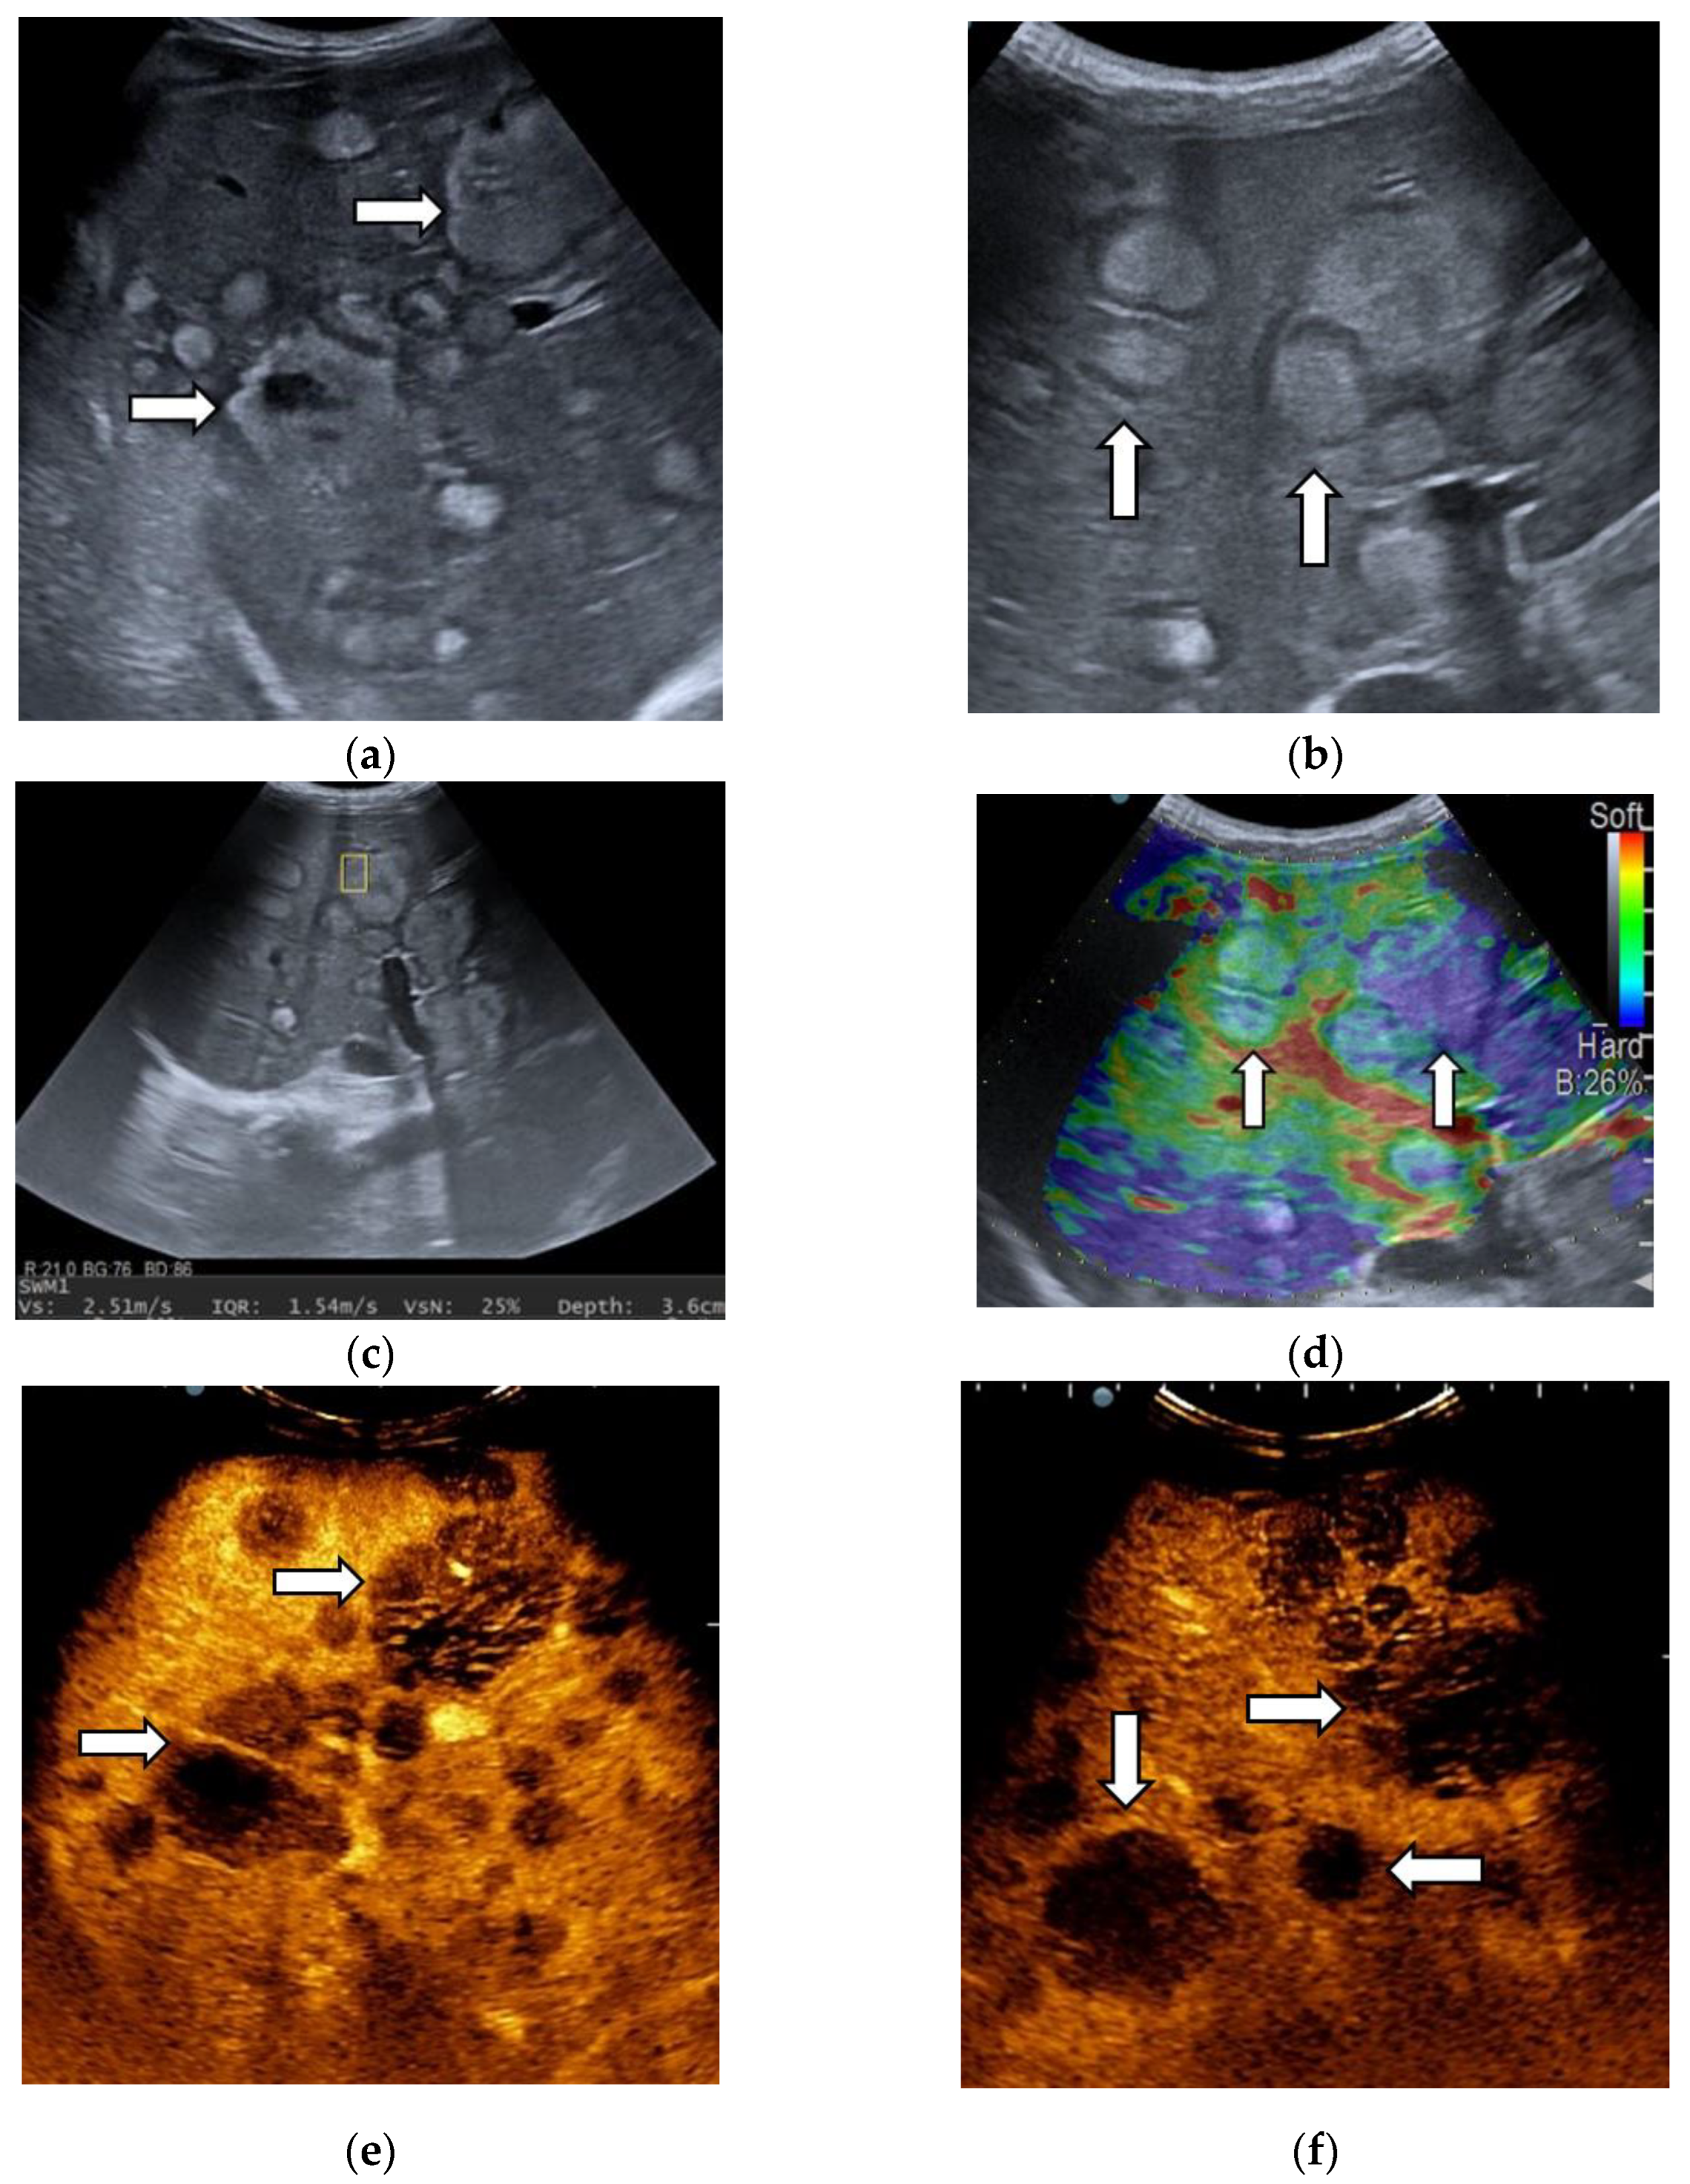

3.1. B-Mode Ultrasound

3.2. Contrast-Enhanced Ultrasound

3.3. Shear Wave Measurements in Liver Tumors

3.4. Real-Time Tissue Elastography